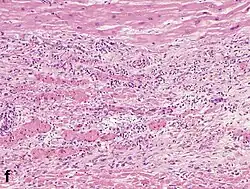

Micrograph of a myocardial infarction (ca. 400x H&E stain ) with prominent contraction band necrosis.

Histopathological examination of the heart may reveal infarction at autopsy. Gross examination may reveal signs of myocardial infarction.

Under the microscope, myocardial infarction presents as a circumscribed area of ischemic, coagulative necrosis (cell death). On gross examination, the infarct is not identifiable within the first 12 hours.[22]

Although earlier changes can be discerned using electron microscopy, one of the earliest changes under a normal microscope are so-called wavy fibers.[23] Subsequently, the myocyte cytoplasm becomes more eosinophilic (pink) and the cells lose their transversal striations, with typical changes and eventually loss of the cell nucleus.[24] The interstitium at the margin of the infarcted area is initially infiltrated with neutrophils, then with lymphocytes and macrophages, who phagocytose ("eat") the myocyte debris. The necrotic area is surrounded and progressively invaded by granulation tissue, which will replace the infarct with a fibrous (collagenous) scar (which are typical steps in wound healing). The interstitial space (the space between cells outside of blood vessels) may be infiltrated with red blood cells.[22]

These features can be recognized in cases where the perfusion was not restored; reperfused infarcts can have other hallmarks, such as contraction band necrosis.[25]